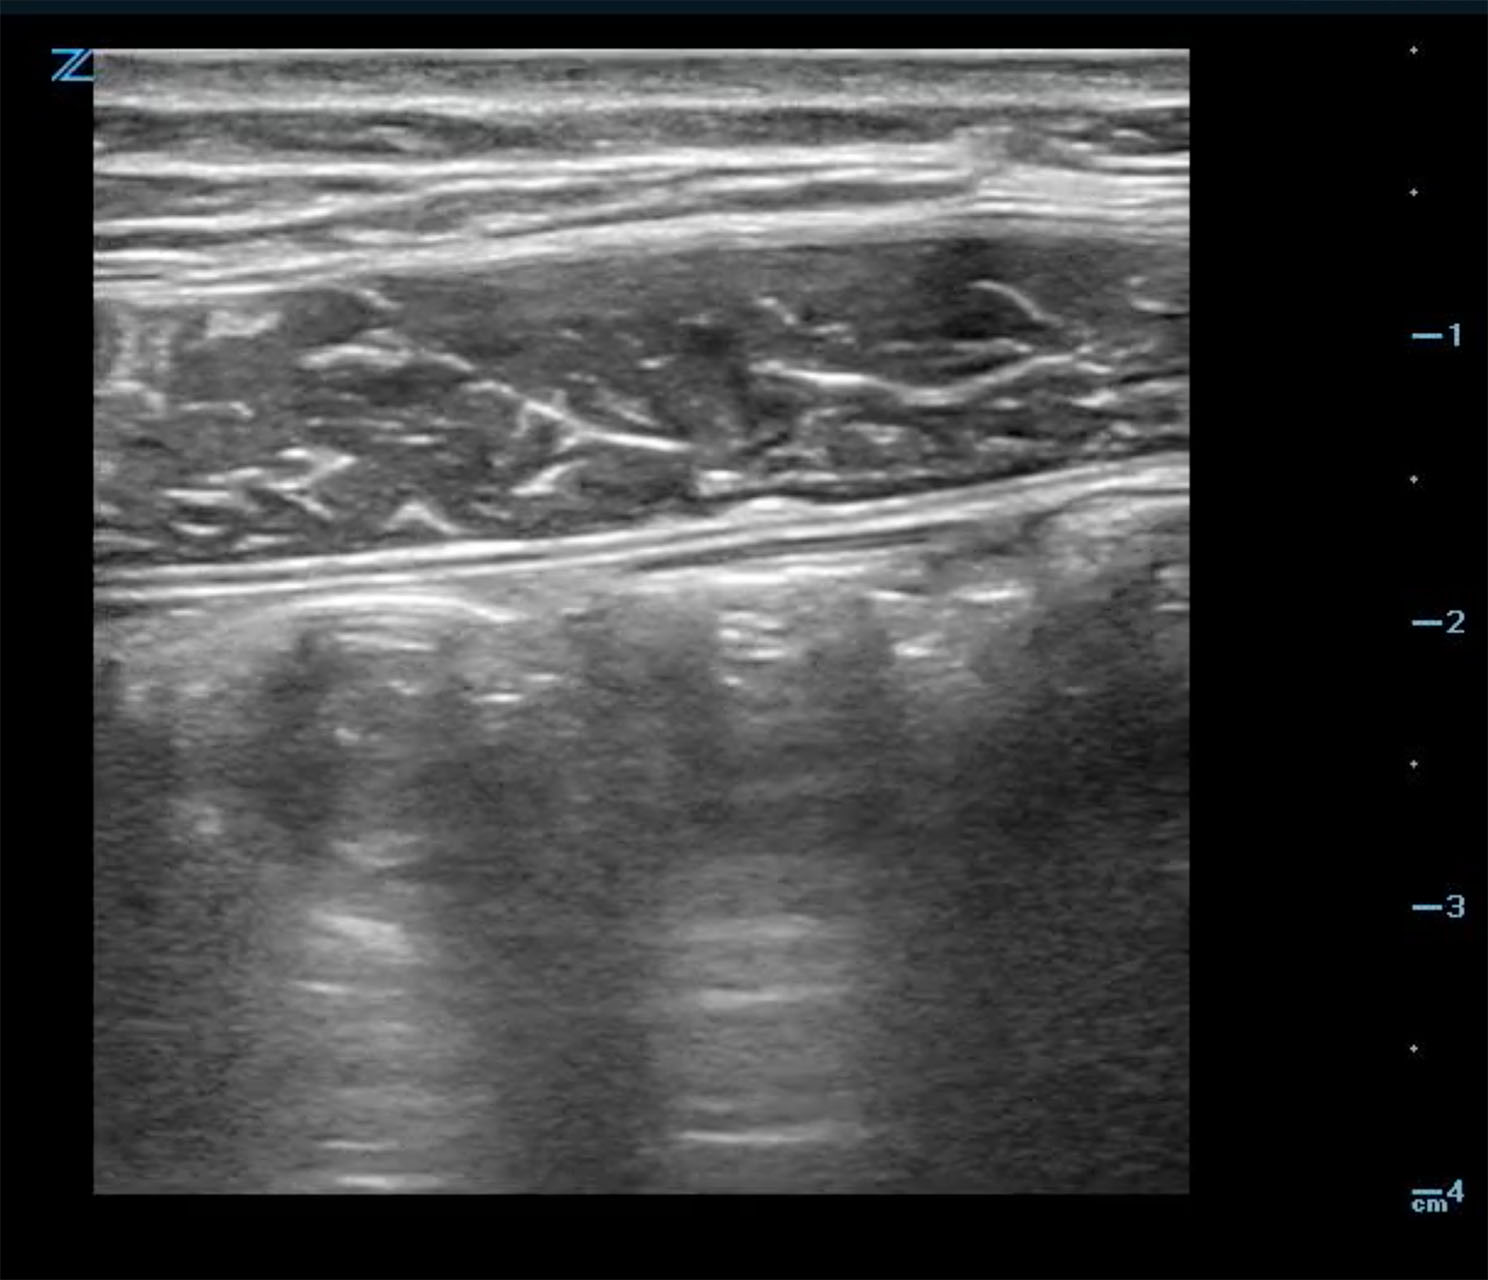

- Normal colon (Fig. 4) has haustra which are seen in the long axis view. Colon can be differentiated from small bowel by size and aperistalsis; but take care to not confuse with dilated loops of small bowel. (Fig. 5)

- Normal bowel often creates artifact due to bowel gas which looks like bright echoes with shadowing. If stool is present it can appear to have mixed echogenicity.8 Notably, identify where the ileum terminates into the cecum.

- Figure 4. Normal colon in long axis view

- Figure 5. Dilated loop of small bowel seen in long axis